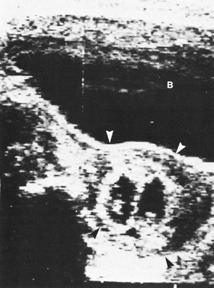

of neurologic deficits (see Fig. 6).  Fig. 6. A: First-trimester twin intrauterine gestations. Ultrasound examination

of the pregnant uterus (arrowheads) shows the “owl eyes” characteristic of early twin pregnancies. B: Maternal urinary bladder. (Courtesy of Alfred B. Kurtz, MD) Fig. 6. A: First-trimester twin intrauterine gestations. Ultrasound examination

of the pregnant uterus (arrowheads) shows the “owl eyes” characteristic of early twin pregnancies. B: Maternal urinary bladder. (Courtesy of Alfred B. Kurtz, MD)

| Fetal number (Fig. 6) |